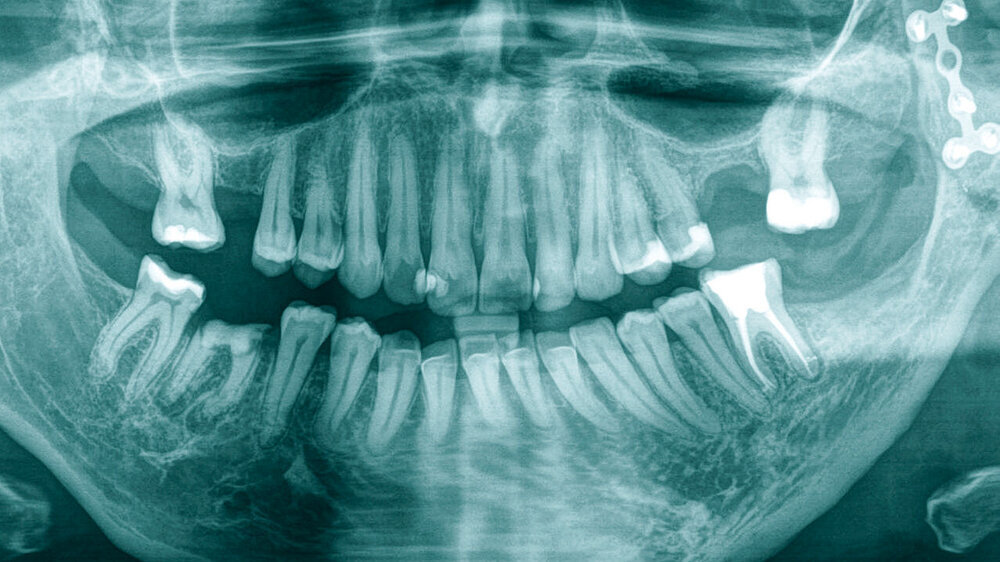

Radiologisch zeigten sich schon im Orthopantomogramm (Abbildung 1) eine deutliche Verschmälerung des gesamten linken Unterkieferbereichs und eine vormals eingebrachte Miniosteosyntheseplatte im Bereich des aufsteigenden Unterkieferastes.